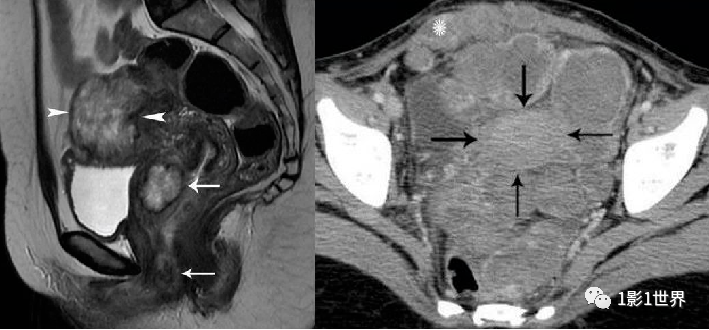

侵袭性葡萄胎,极少数绒毛变性可侵入到肌层,甚至发生远处转移。从组织学上看,属于水泡状胎块,不属于肿瘤。

影像诊断

MRI检查

子宫肌层受压变薄,结合带完整

增强扫描:表现为在扩张的子宫内膜腔内含有多个小囊腔样强化的异质组织,动脉期轻度不均匀强化,静脉期及延迟期渐进性网格状强化;宫旁见多发迂曲流空信号影,增强后可呈血管样强化